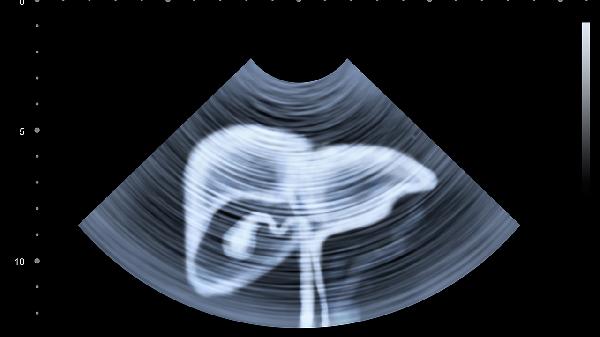

脂肪肝这个"沉默的杀手"正在偷袭年轻人。数据显示,20-40岁人群脂肪肝患病率十年间翻了三倍。更可怕的是,约15%的单纯性脂肪肝会悄悄发展成脂肪性肝炎,其中又有20%可能进展为肝硬化。

2、每年做肝脏弹性检测

无创的FibroScan能准确评估肝纤维化程度,比B超更敏感。